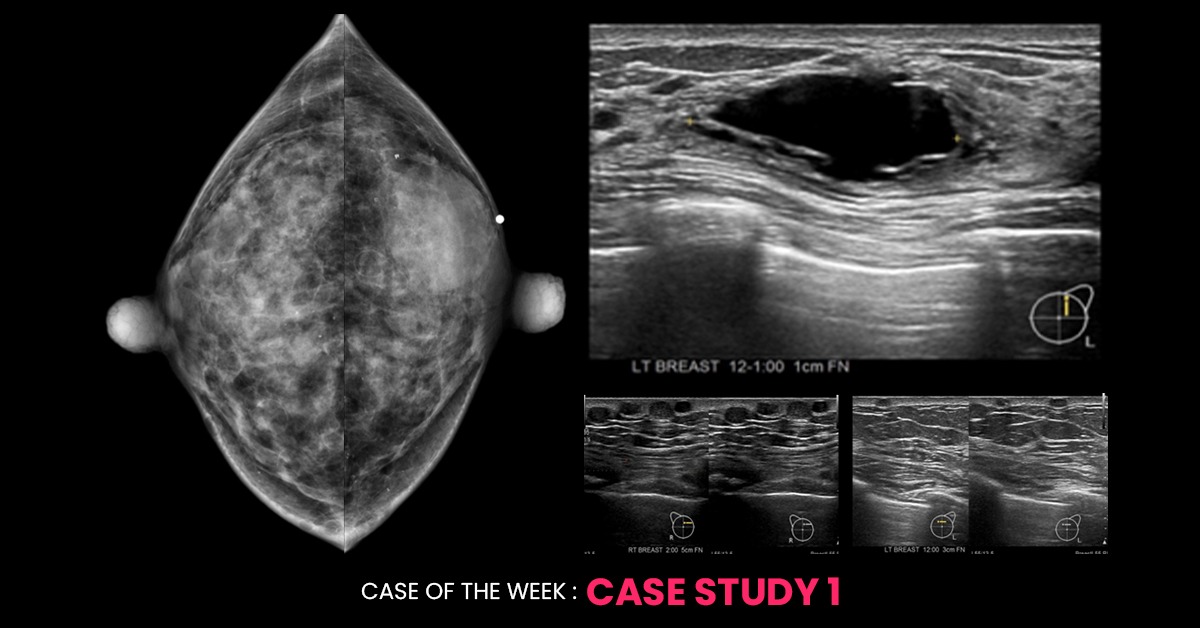

46-year-old woman with a palpable left breast lump. Mammogram and ultrasound of both breasts are shared. Diagnosis? What would you do next to confirm the diagnosis? BI-RADS?

Beneath the area of palpable concern in the left breast, an oval, circumscribed, isodense mass is evident on the mammogram. Ultrasound examination reveals a cyst in the left breast, correlating with this lesion. Additionally, numerous round, circumscribed, fat-density lesions are diffusely distributed in both breasts. The differentials include multiple sebaceous cysts or free fat injection. Ultrasound examination reveals bilateral, multiple, circumscribed, iso to hypoechoic masses in the intradermal layer in both breasts, correlating with these fat density lesions observed on the mammogram. This confirms the lesions as multiple sebaceous cysts, a condition known as “Steatocystoma Multiplex.”

A simple clinical examination of the patient may reveal multiple small cutaneous lesions on the chest, arm, and occasionally other parts of the body, aiding in clinching the diagnosis. As this condition is autosomal dominant, a similar family history may be present. Steatocystoma Multiplex is benign and typically does not require intervention or follow-up. Therefore, the final BI-RADS assessment in this patient will be BI-RADS 2 (Benign condition). Aspiration of the palpable left breast cyst may be offered for symptomatic relief if clinically indicated.